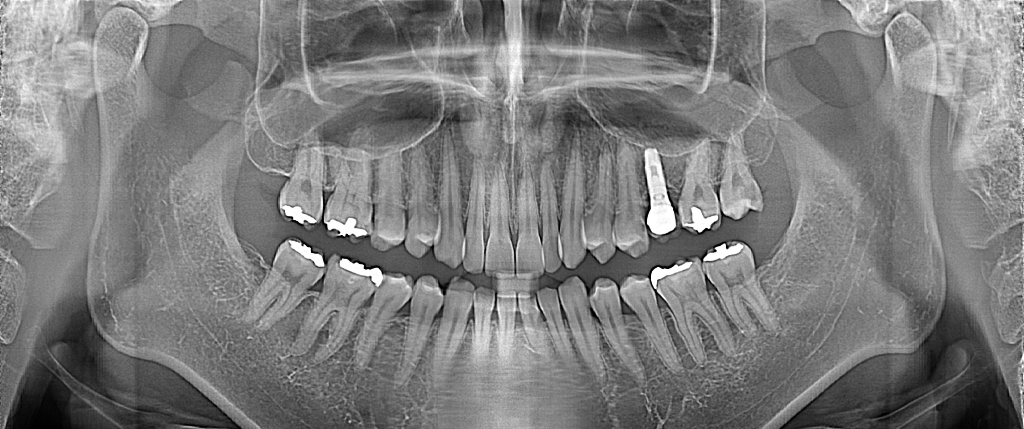

그 외 크기는 특별히 아주 크거나 그렇지는 않아보입니다만 방사선 사진말고 일반 입 안 사진도 있으면 좀 더 도움되는 답변 드릴 수 있을 것 같습니다

3. 상황을 알 수 있도록 가능하다면 이전 치과에서 촬영한 치과방사선사진을 다 받아서 새로운 치과에 보여주셔도 좋습니다